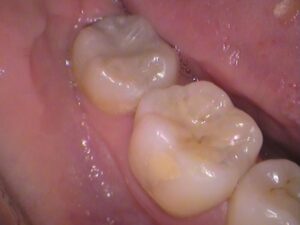

例えば、この写真には黒いところが何か所かあります。

これは虫歯でしょうか?

その①歯の溝の黒

矢印の歯ですが、

患者さんの多くが虫歯かと悩む、このような歯。

歯に黒く筋が入っています。

これは溝に入り込んだ「着色」で虫歯ではありません。